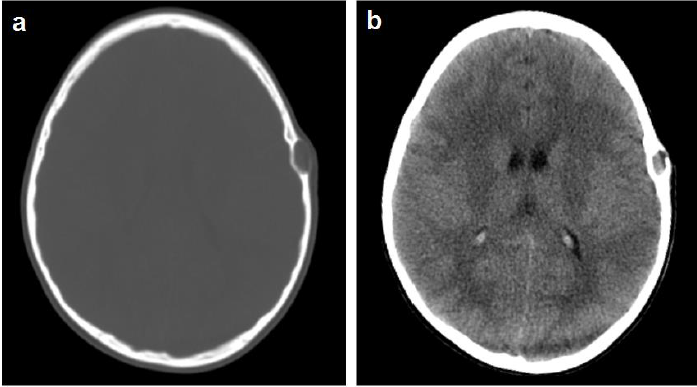

En estudio de Tomografía Computarizada simple de cráneo realizada un mes previo al acto quirúrgico valorada en cortes axiales y coronales se observa en ventana ósea lesión ocupante de espacio (LOE), hipodensa, extradural de forma ovoidea, de característica lítica, ubicada en región parietal izquierda con aproximadamente 8,8x17 mm de diámetro. Ventana parenquimatosa sin alteraciones (Fig. 1a, 1b). En resonancia magnética cerebral contrastada se observa imagen extradural, de forma ovoidea, bien delimitada con bordes regulares de características quísticas en región parietal izquierda, de comportamiento heterogéneo, hipo e isointensa en secuencia T1, hiperintensa en T2 y FLAIR, sin captación tras la administración de contraste endovenoso y restricción en Difusión (Fig. 2). Se realizó reconstrucción 3D postquirúrgica donde se observa defecto óseo en hueso parietal izquierdo (Fig. 3).